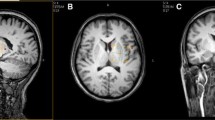

The influence of iron deposits on T2 values and the content of metabolites in the brain of three patients with DNA proved pantothenate kinase-associated neurodegeneration (PKAN, formerly Hallervorden-Spatz syndrome) was studied. An eye-of-the-tiger sign, a typical MR finding for PKAN, was observed in two patients with the same mutation. A hypointensive lesion in a whole globus pallidus was observed in the third patient with the additional mutation. T2 values in the globus pallidus of the patients were about 40% shorter than in controls (71/48 ms in controls vs. patients), which corresponds to the increase of Fe concentration based on the ferritin basis from 17 mg for controls to 48 mg (100 g wet brain weight) in PKAN patients. 1H MR spectroscopy (MRS) has mainly been used to describe neuronal damage represented by decreased NAA (6.4 mmol vs. 9 mmol) and Cr/PCr (7.0 mmol vs. 9.8 mmol) concentrations in the basal ganglia region of the patient group to controls; MRS is much more case-sensitive and describes individual development of the disease as demonstrated in the difference between the spectra of typical PKAN patients (1, 2), and the patient (3) with atypical PKAN development. Any significant changes of metabolite concentration with the exception glutamine, glutamate and GABA were found in the white matter.